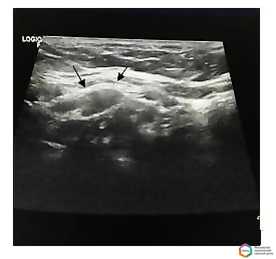

У 127 (83,6%) пациентов при проведении ультразвуковых исследований были выявлены подозрительные на злокачественное поражение лимфатические узлы. В 69 (45,4%) случаях подозревалась злокачественная лимфома. Визуализировались множественные увеличенные периферические лимфатические узлы нескольких зон, многие из них были спаяны между собой (рис. 2).

Рисунок 2.

Лимфоузлы шеи при лимфогранулематозе